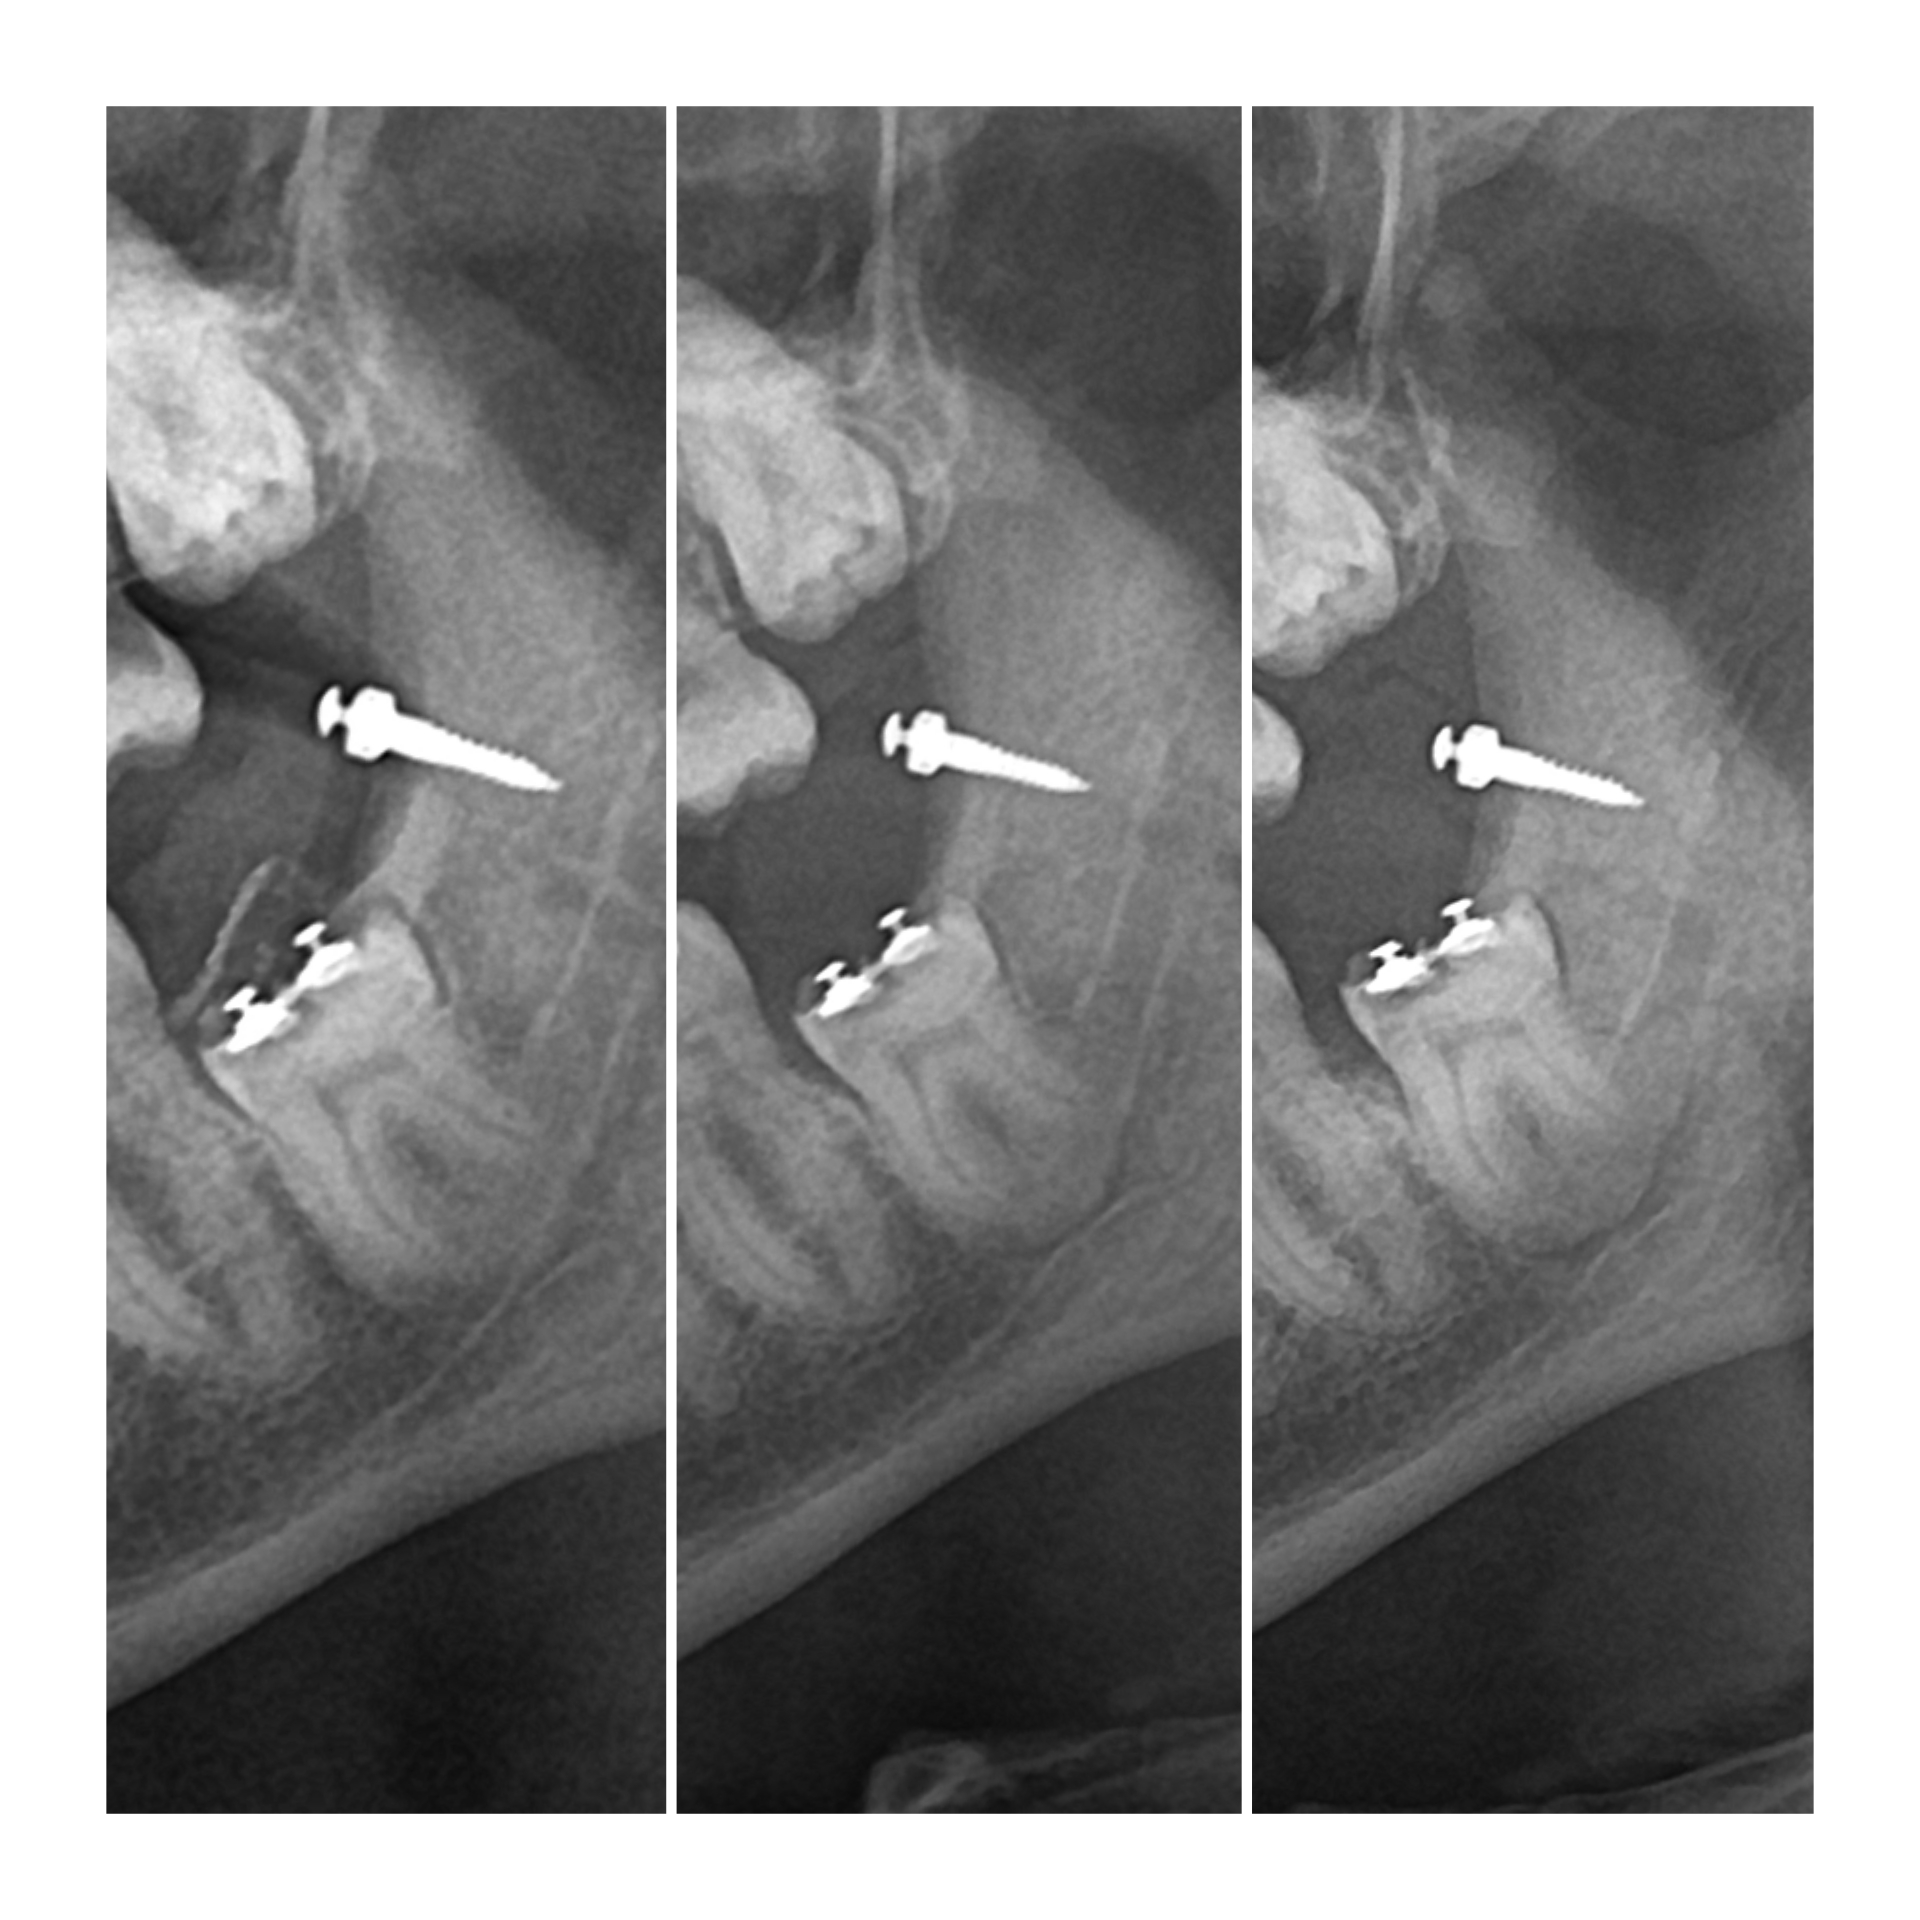

По данным ортопантомограммы (ОПТГ), проведенной через 7 недель после начала лечения, отмечалось недостаточное перемещение зуба.

ОПТГ через 7 недель. Уже заметен контур корня в области апекса.

Через 11 недель на ОПТГ наблюдалось незначительное, но прогрессирующее перемещение зуба.

ОПТГ через 0 , 7 , 11 недель. Заметна динамика.

К 14-й неделе лечения на ОПТГ было зафиксировано значительное  смещение  зуба, достаточное для его удаления.

ОПТГ на 14 неделе